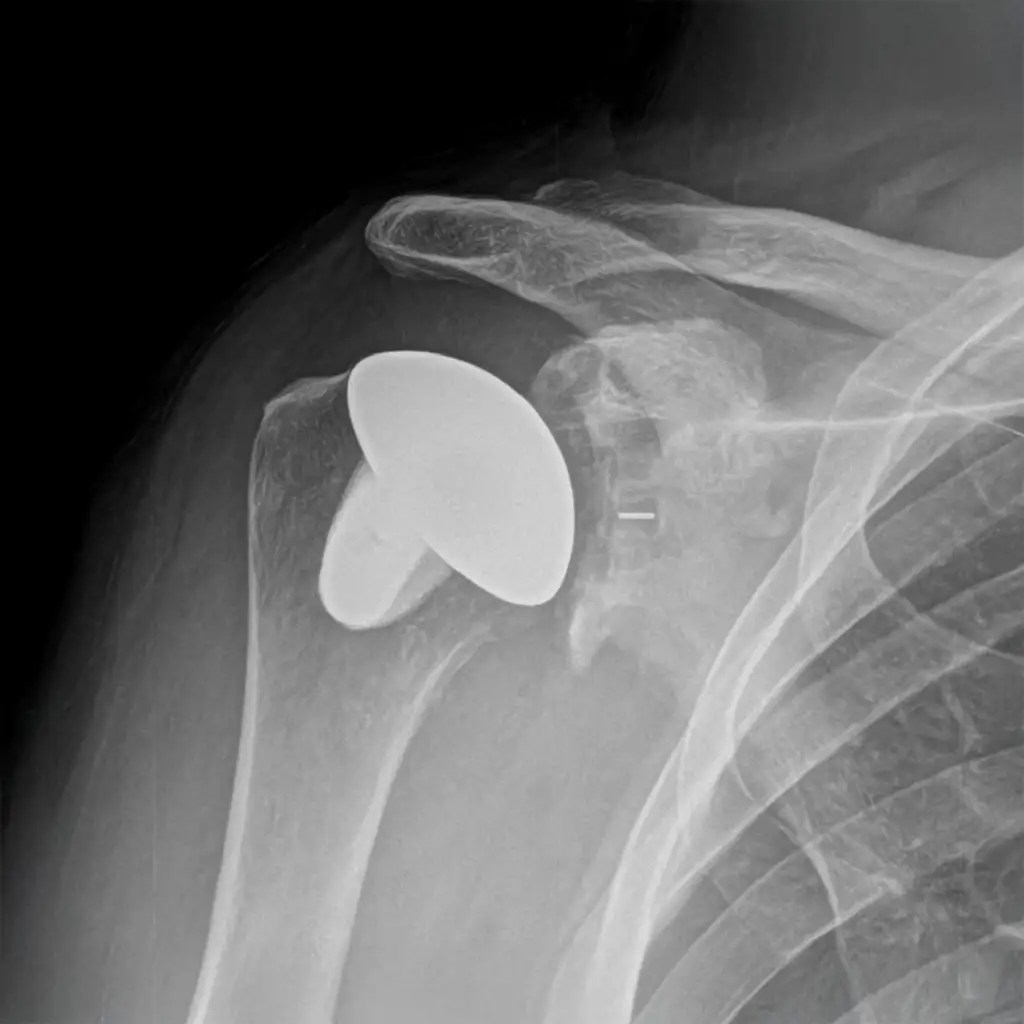

Total shoulder replacement addresses advanced arthritis by replacing both the ball and socket of your shoulder joint. The procedure recreates your natural shoulder anatomy to restore smooth, pain-free movement when daily activities become difficult.

Reverse Shoulder Replacement

Reverse shoulder replacement treats severe rotator cuff damage, complex fractures, or advanced arthritis by switching joint mechanics. Reversing the ball and socket allows other muscles to stabilize the shoulder and restore strength, motion, and daily function.